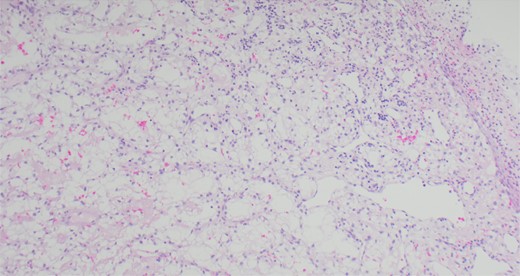

A 63-year-old male with a medical history of hypertension and progressive dyspnoea on exertion, underwent a computed tomography (CT) angiogram for the workup of a pulmonary embolism. There was an incidental finding of a 12-cm left renal neoplasm (Fig. 1), extensive metastatic nodal abdominal disease and bilateral metastatic pulmonary disease (T3 N2 M1). He was discussed at the Urology multidisciplinary team meeting (MDT) and commenced on Sunitnib, given the dissemination of disease. Repeat imaging showed a significant reduction in size of the pulmonary metastasis. Following which, he underwent a cryo-reductive nephrectomy that confirmed a clear cell RCC 102 mm, Grade 3. Development of a tongue lesion after a year warranted Otorhinolaryngology input. Clinical assessment with flexible nasendoscopy depicted a 0.5 cm by 0.5 cm pedunculated lesion on the midline of the tongue (Fig. 2). A biopsy under local anaesthetic confirmed a clear cell RCC (Fig. 3) that was positive for AE1/AE3, Vimentin (Fig. 4) and EMA. Further CT imaging, 1 month after the biopsy confirmed left hilar nodule progression from 2.3 to 3 cm. The medical oncology MDT recommended commencing Nivolumab. Following recurrent bleeding from the tongue, radiation to the area was determined to be the best treatment modality. The patient is still clinically well and tolerating oral intake with no significant large bleeds to date. Regular medical oncology, radiation oncology, urology and Otorhinolaryngology follow-up is ongoing, however, the prognosis is poor with such disseminated disease and the primary focus is on minimising morbidity.

Immunohistochemical staining confirming Vimentin positivity and the presence of malignant RCC over a benign Oncoytoma.

The main histological subtypes of RCC are clear cell, papillary, chromophobe, collecting duct carcinoma, medullary carcinoma and unclassified [6]. Distinction between clear cell salivary tumours and RCC should be made prior to treatment, as histologically, this can be difficult to perform on standard light microscopy. A strong reaction to Vimentin will confirm this on immunohistochemical staining [7]. To find an RCC metastasis on the tongue is rare; the oral cavity consists of the anterior two thirds of the tongue, the lips, the floor of mouth, hard palate, buccal mucosa, maxillary and mandibular alveolus and the retro molar trigone. One of the theories regarding metastatic spread of RCC is that Batson’s venous plexus extends from the skull to the sacrum. This valveless system theoretically offers less resistance to the spread of tumour emboli, especially when there is an increase in intrathoracic and intra-abdominal pressure, allowing retrograde flow by-passing the pulmonary filters [8].